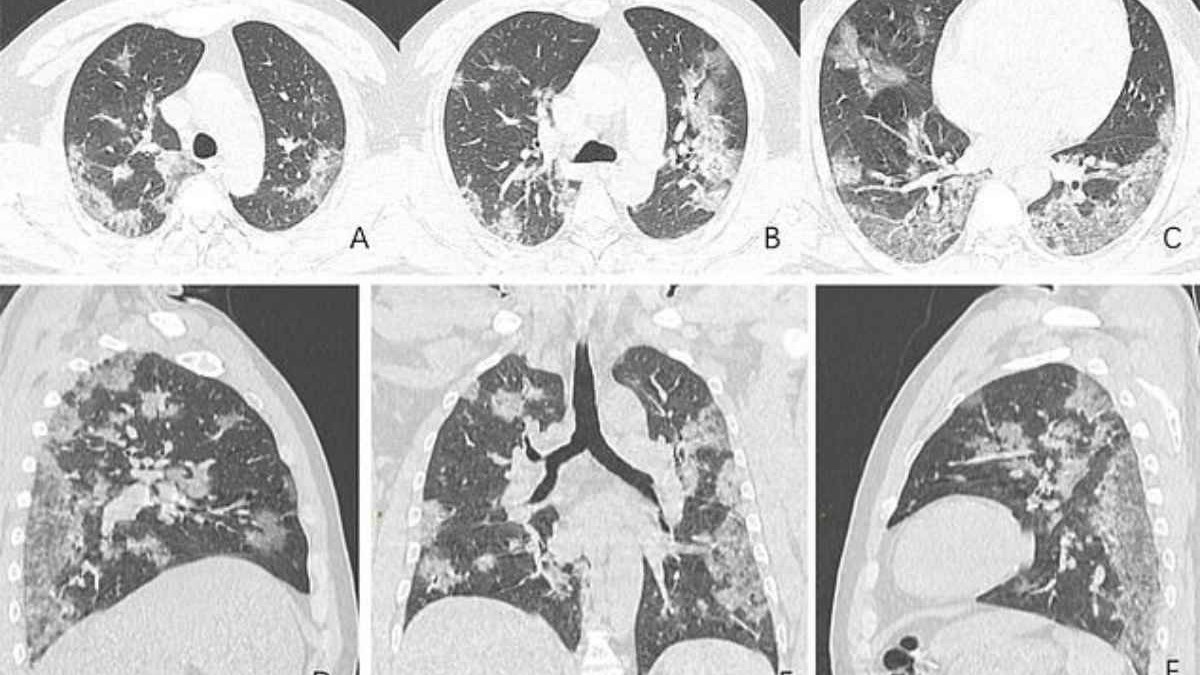

44 жастағы Қытай тұрғынының өкпесіне жасалған рентген мен компьютерлік томографияның суреттері оның ағзасында қандай өзгерістер болғандығын көрсеткен. Дәрігерлердің айтуларынша, коронавирусқа шалдыққандардың өкпесі рентген суреттері ЖРВИ мен MERS жұқтырғандардікіне ұқсайтынын аңғартқан.

Мамандар көз жұмған азаматтың Уханьда балық базарында саудагер болып жұмыс істегенін айтады. Суреттерде азаматтың өкпесінің төменгі жағында ірі-ірі қара дақтар байқалады. Бұған қоса өкпеде әлдебір сұйықтықтың бар екендігі расталыпты. Солтүстік Американың радиологиялық қауымдастығы таратқан суреттерде әлгі сұйықтықтың уақыт өте келе көлемі ұлғайғаны аңғарылады.

Індетке тап болған азамат 25 желтоқсанда карантинге жатқызылып емделсе де, бір апта болмай жатып көз жұмыпты.

54 жастағы Уханьда коронавирус жұқтырған әйелдің өкпесінде де дәл осындай өзгерістер байқалыпты.

Ал ауруға шалдыққан 45 жастағы азаматшаның өкпесінде ақ дақтар пайда болған.